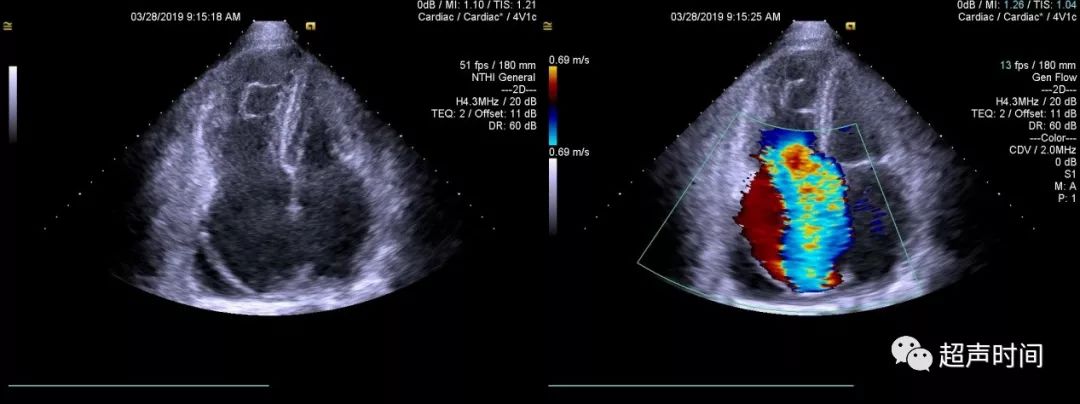

右位心超声,右位心的超声模板

右位心完全性大动脉转位伴二尖瓣下移超声表现1例